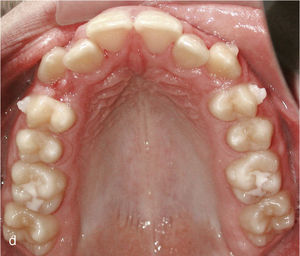

La expansión transversal constituye una alternativa a la reducción de esmalte interproximal para corregir apiñamientos y para dotar a las arcadas de un aspecto armonioso. La figura 4a muestra un maxilar estrecho en el plano transversal y dientes muy rotados y apiñados en el sector anterior. En este caso fue posible lograr una arcada armoniosa utilizando anclajes en los dientes 14, 13, 23 y 24 con ataches verticales, expansión transversal, protrusión del diente 21 y reducción del esmalte interproximal (fig. 4b).

Sector anterosuperior con dientes 11 y 21 en mesioversión y triángulo negro interdental (a). Se colocaron ataches rectangulares verticales en los dientes 11 y 21 y en los anteriores adyacentes. Resultado del tratamiento después de enderezar los dientes 11 y 21 y de cerrar el triángulo negro (b).